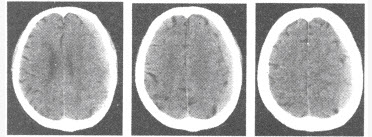

男,25岁,外伤后行CT检查,最可能的诊断为()

A:脑膜瘤

B:脑挫裂伤

C:蛛网膜下腔出血

D:硬膜下血肿

E:硬膜外血肿